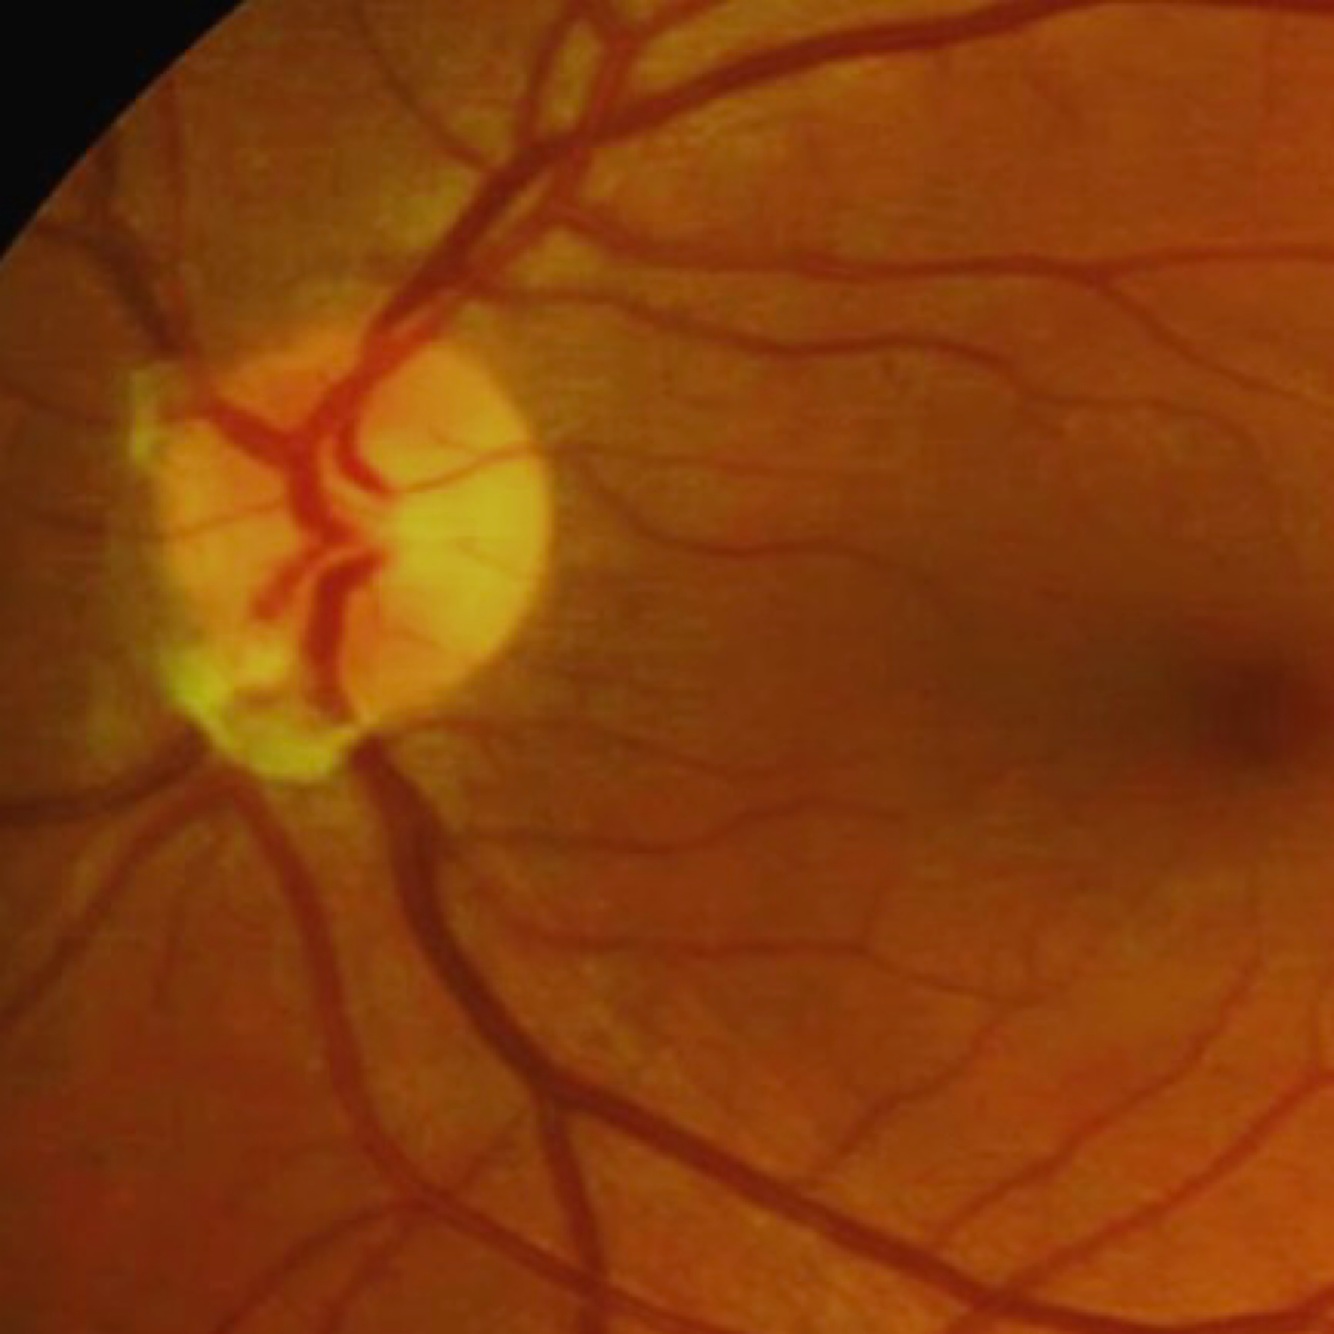

Myelinated nerve fiber layer

* white feathery margins typically extending from the optic disc